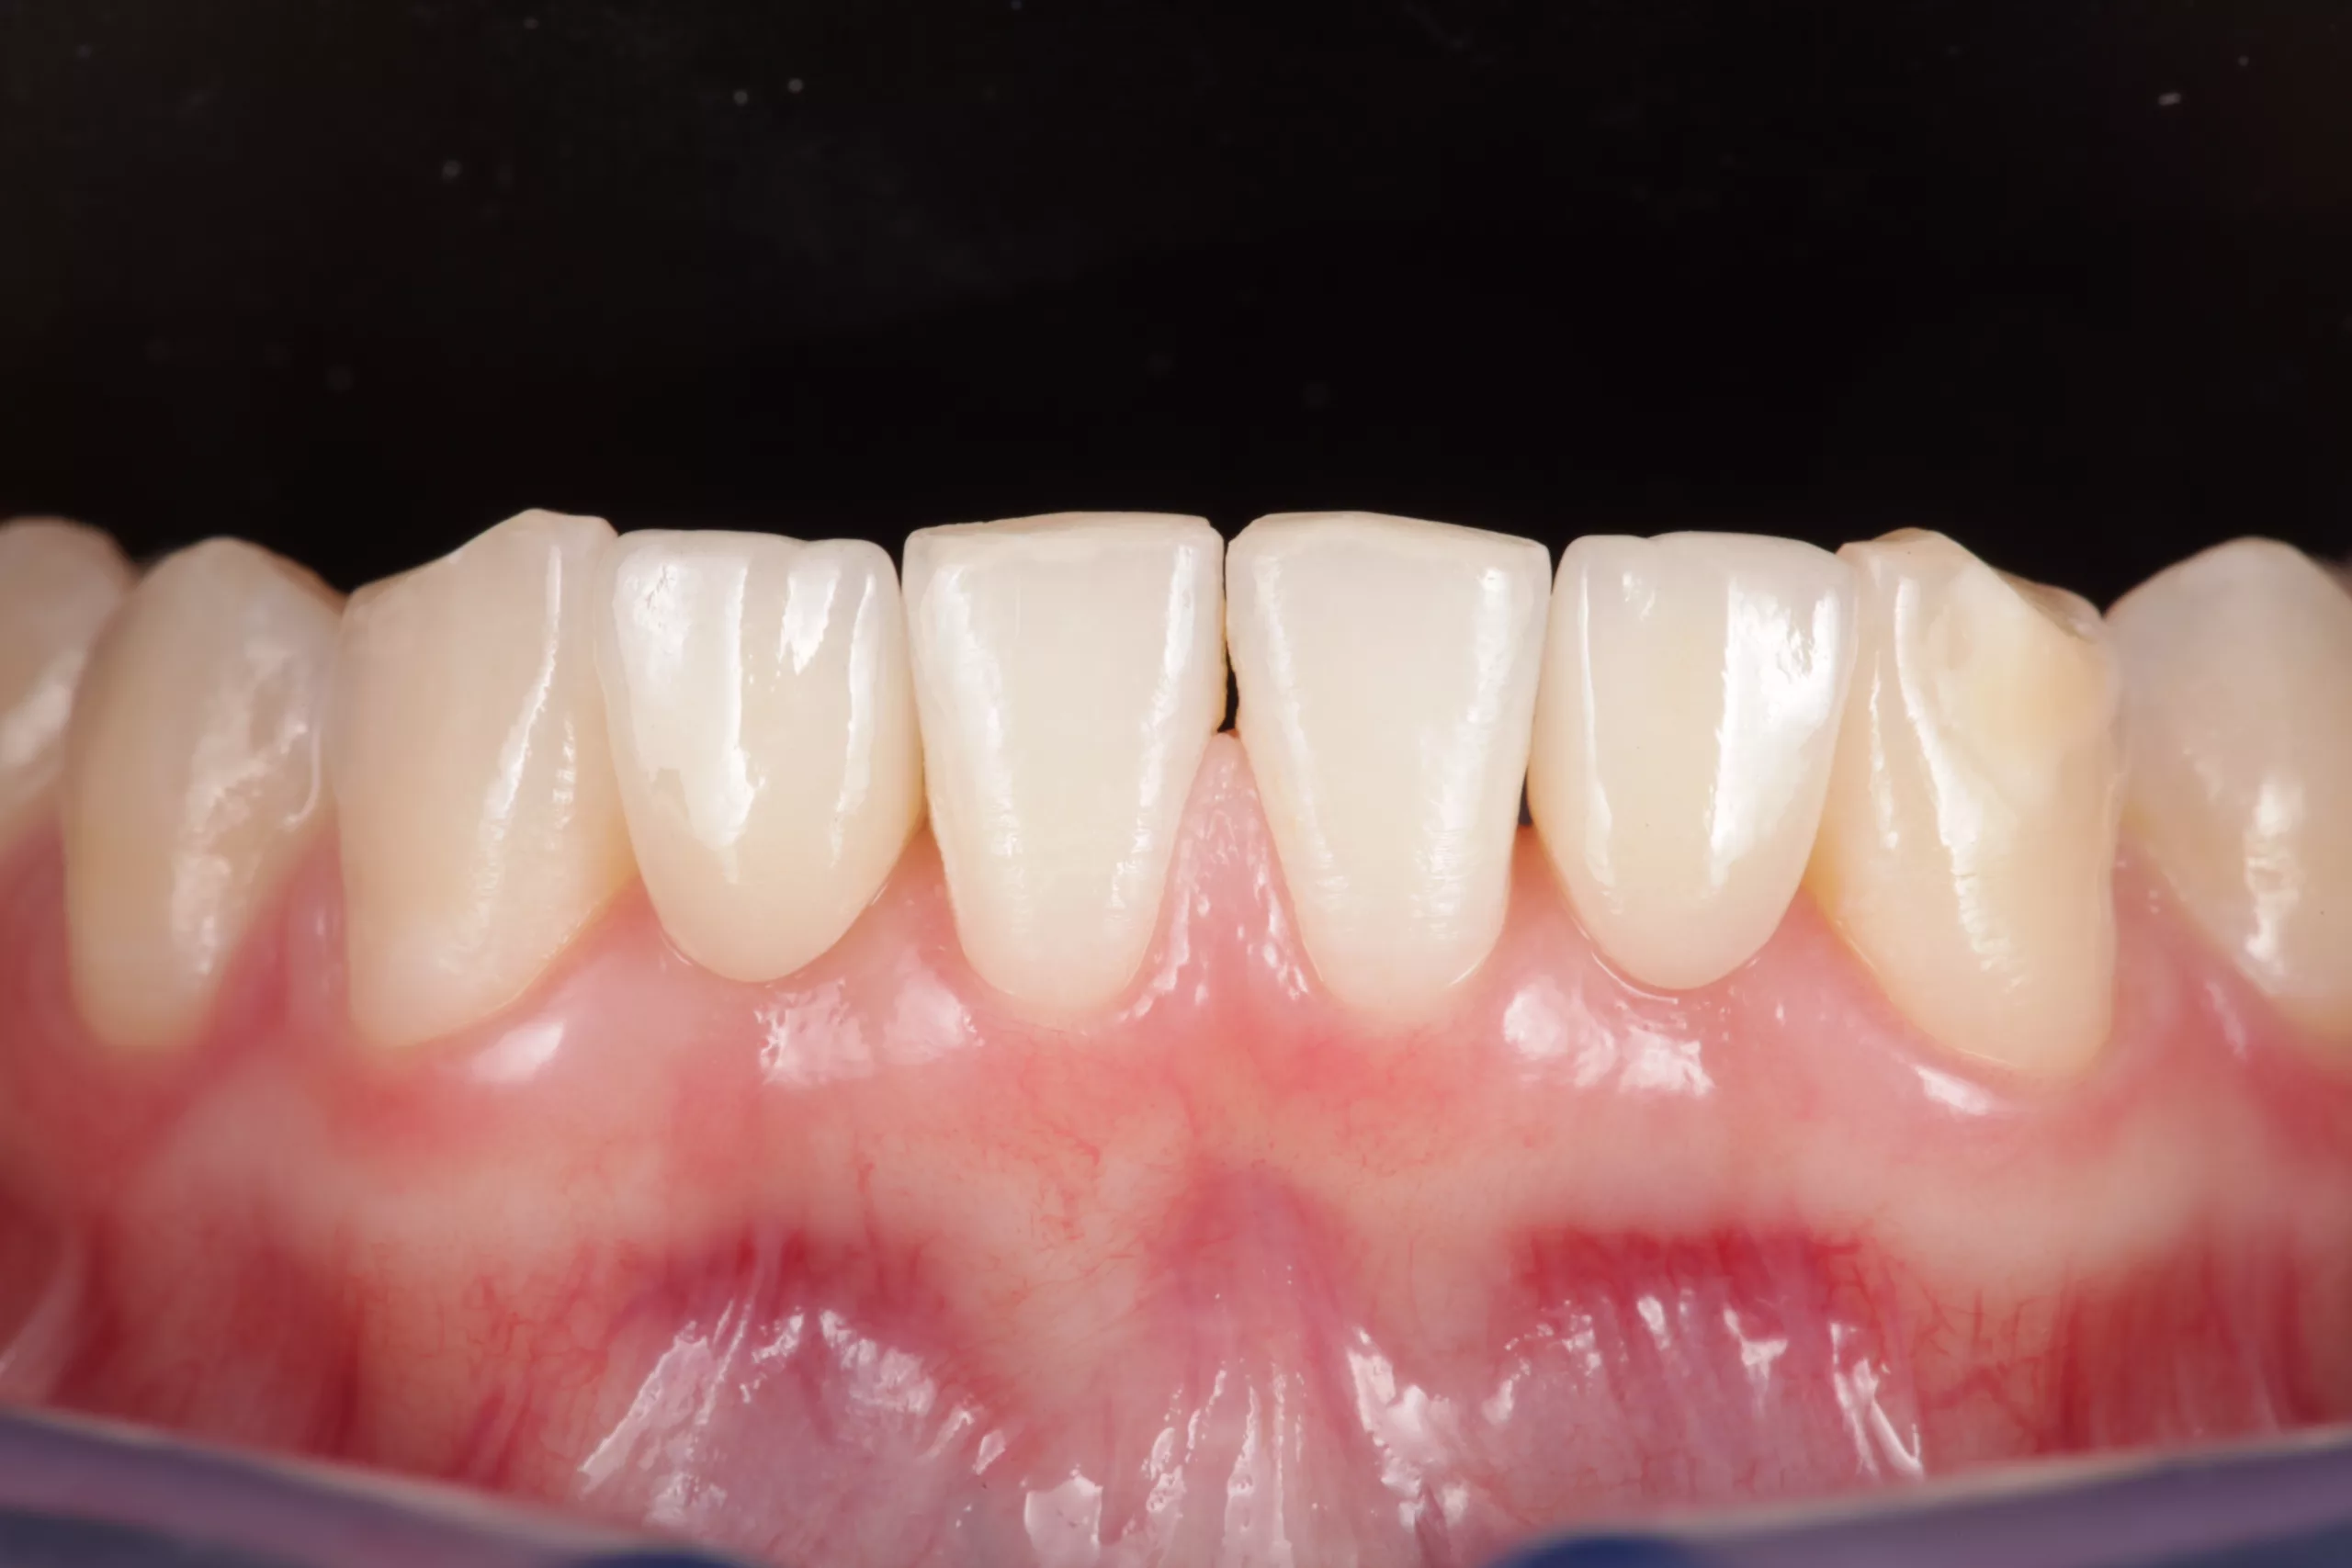

Okklusion und Artikulation können nun überprüft und ggf. angepasst werden. Abschließend folgt die Instruktion des Patienten zur effizienten Reinigung im Bereich der Adhäsivbrücke. Eine Situationsabformung mit anschließendem Situationsmodell und die fotografische Dokumentation des klinischen Ergebnisses helfen bei den Nachsorgesitzungen zur Kontrolle etwaiger Veränderungen der Pfeilerzahnstellung (Abb. 13- 15).